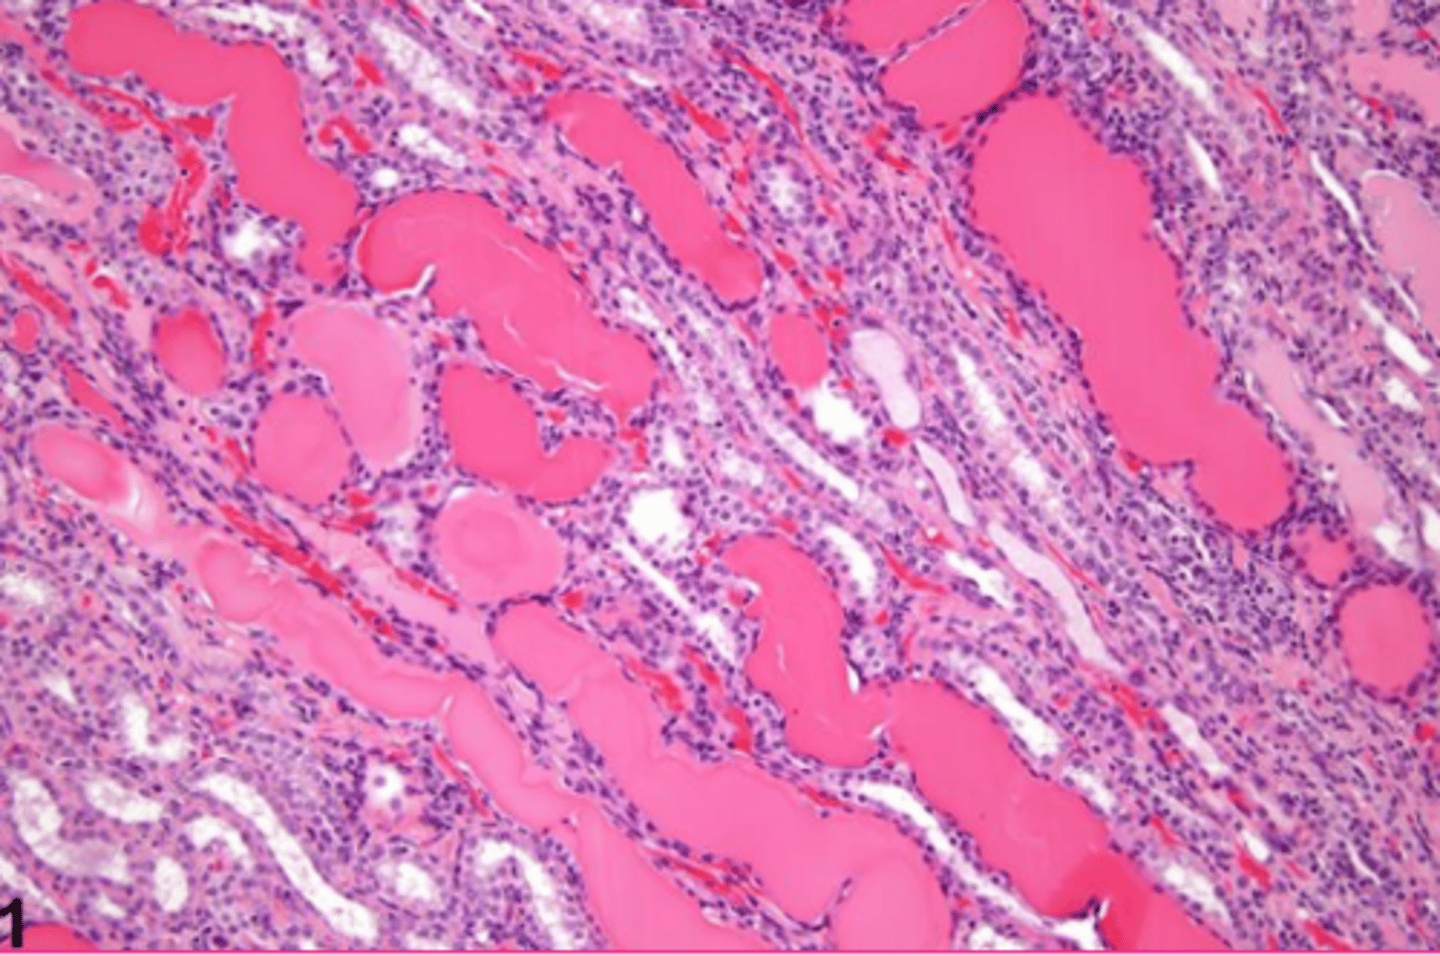

hyaline casts

What extracellular accumulation?